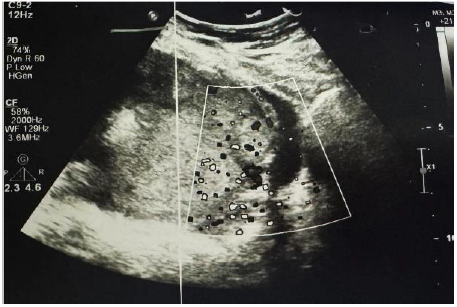

In the operating room, a midline incision was extended above the umbilicus due to severe adhesions. Given the extensive placental invasion, a fundal incision was performed to deliver the fetus. A breech female infant weighing 1690 grams with an Apgar score of 8-9 was delivered during a two-hour-long cesarean delivery operation. Due to severe lower uterine segment adhesions, a hysterectomy was performed (Figure 3). The placenta was not removed and was kept in situ. The uterus and placenta were successfully removed intact, with the cervix visible, as shown in the attached images (Figure 4). The cervix was clearly identifiable, and both ovaries were preserved, considering the patient’s age. Estimated intraoperative blood loss was approximately 2,000 ml, and one unit of packed red blood cells was transfused based on an anesthesiologist’s assessment. The fully extracted placenta was transferred to the pathology laboratory for further study. The patient had an uneventful postoperative recovery and was discharged from the hospital on postoperative day 3.

Figure 4. Intraoperative image showing the uterus and placenta removed en bloc, with clear visualization of the cervix